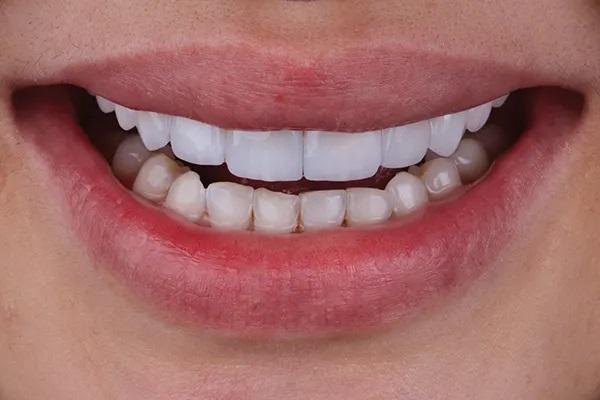

Фото 14. Вид окончательных реставраций в полости рта, после фиксации.

Фото 15. Улыбка пациентки после лечения вид спереди.

После примерки внутренние поверхности реставраций были протравлены плавиковой кислотой в течение 20 секунд и силанированы в соответствии с инструкциями производителя, а поверхности опор из диоксида циркония были обработаны воздушно-дисперсионной обработкой и специальной керамической грунтовкой в соответствии с APC (воздушно-абразивная обработка, грунтовка с MDP, цемент из композитной смолы) технология склеивания с диоксидом циркония. Была выполнена адгезионная цементировка по протоколу фиксации на полимерный цемент двойного отверждения, стойкого к изменению цвета и имеющего четкий оттенок (Фото 14 – Фото 18).